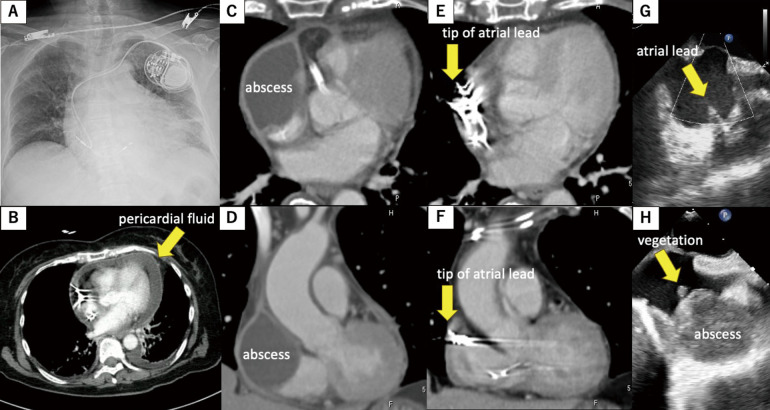

DDD起搏器植入5个月后急性细菌性心包炎。

Acute Bacterial Pericarditis 5 Months After Implantation of a DDD Pacemaker.